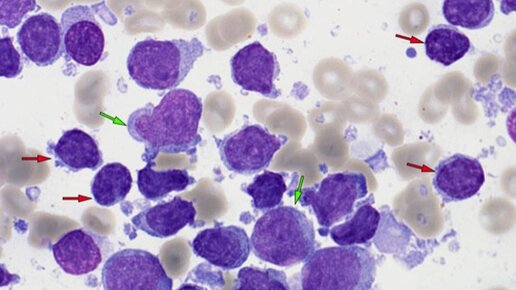

Синдром Рихтера проявляется быстрым прогрессированием хронического лимфоцитарного лейкоза в более агрессивную форму лимфомы. Синдром Рихтера обычно связан с плохими показателями выживаемости, однако лечение может помочь человеку достичь кратковременной ремиссии. Что такое синдром Рихтера? Хронический лимфоцитарный лейкоз (ХЛЛ) — это тип рака, который поражает белые кровяные тельца (лейкоциты). Синдром Рихтера возникает, когда ХЛЛ быстро трансформируется в агрессивную форму лимфомы (разновидность рака лимфатической системы)...